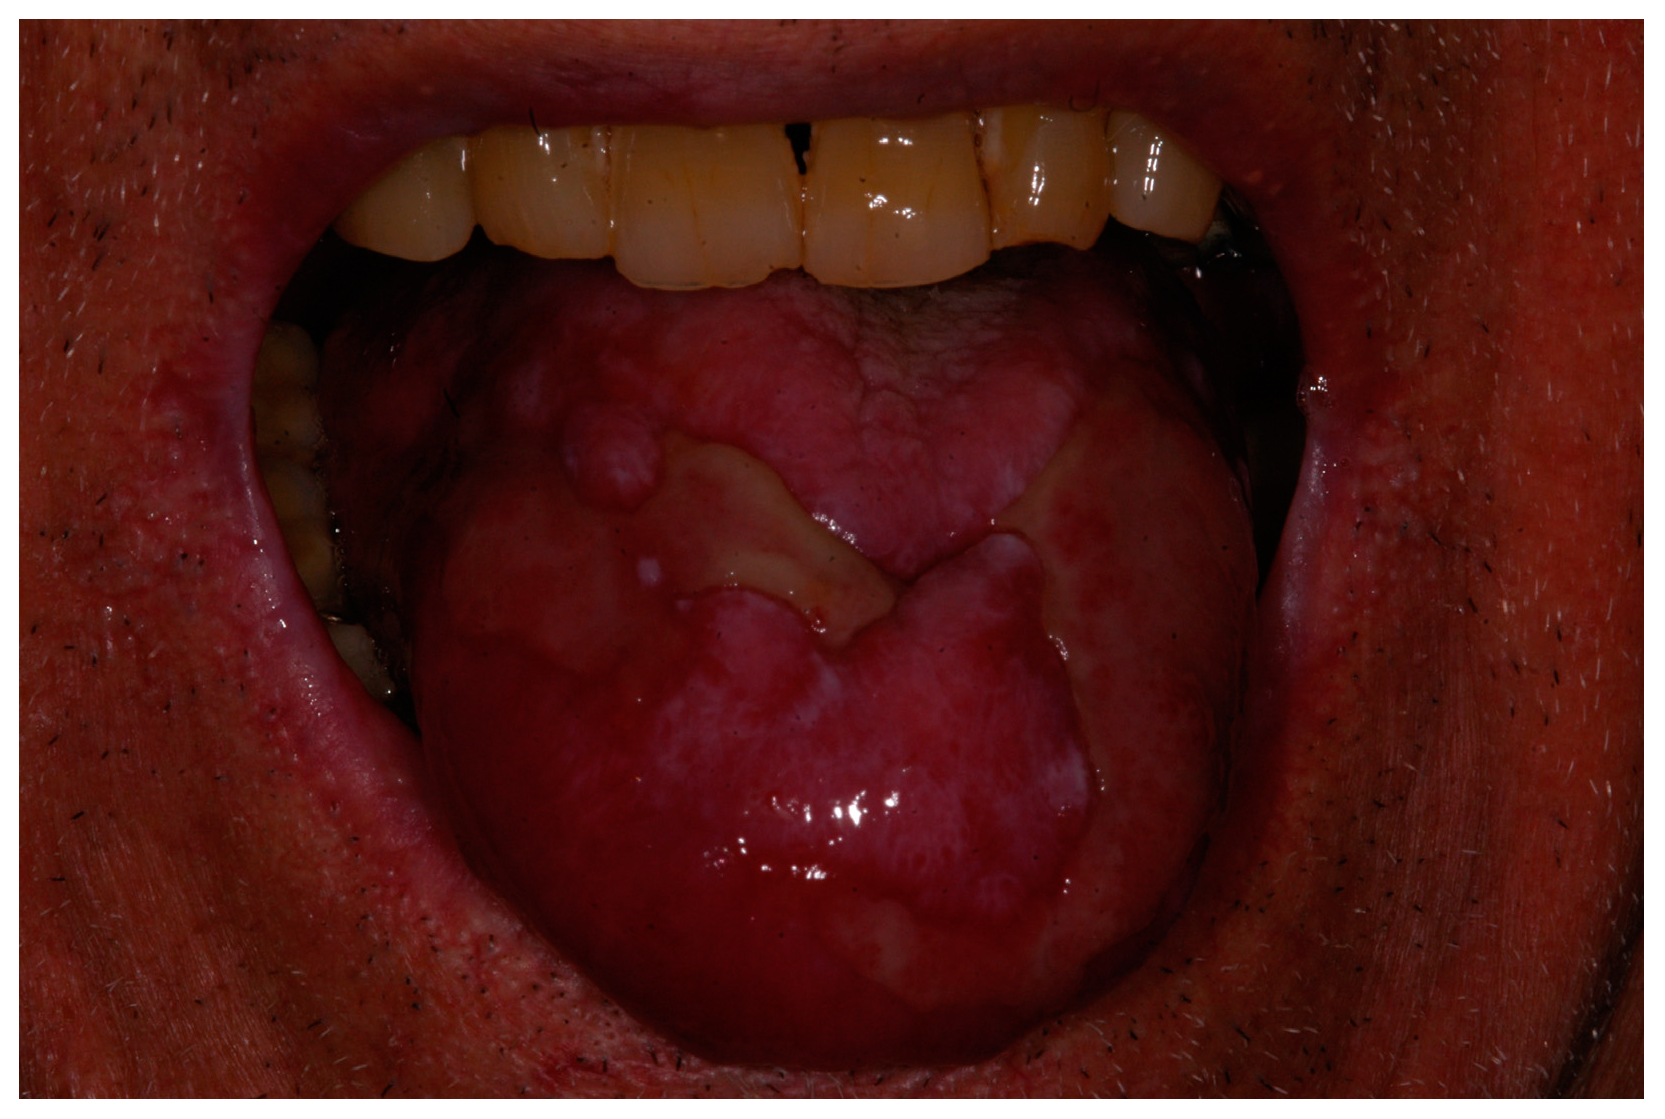

2. Description of the Case